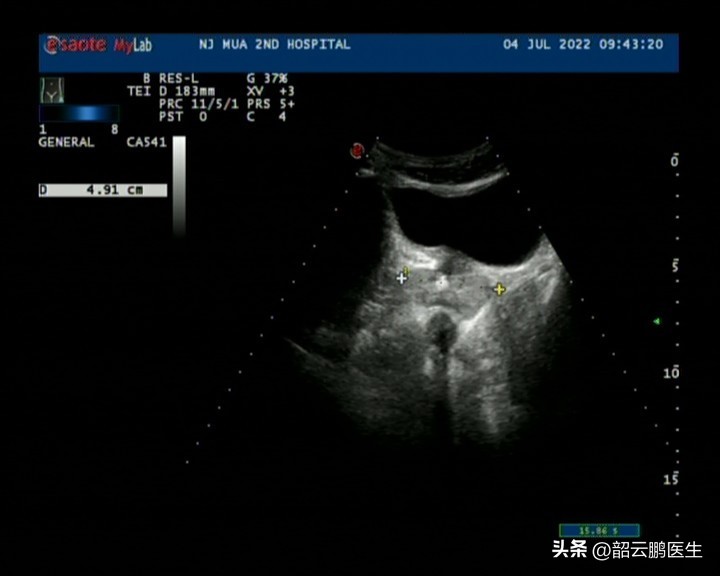

病例二:膀胱頸狹窄

相較于前列腺增生而言,膀胱頸狹窄知道的人就比較少了。病例二因為排尿困難的問題已經有5年的就醫經歷,一直是按照前列腺增生來進行藥物治療的,但是一直治療效果欠佳。這次來院后我們也安排了彩超檢查,提示前列腺體積4.9*3.6*3cm,殘余尿110ml。可以發現相比于第一個病例,雖然前列腺體積變化不大,但是殘余尿量明顯增加了,提示膀胱出口阻力更高。

結合既往的治療病史,我們同時安排了膀胱鏡檢查,鏡下我們不難看出,前列腺的左右側葉和中葉都沒有對尿道產生梗阻的影響,可以說前列腺部的尿道是非常寬敞的。但是膀胱頸部我們可以看到出現了一個類似于狹窄的情況。這也就是為什么他在經歷了前列腺增生藥物治療長達五年之久也沒有癥狀改善,因為雖然他彩超提示前列腺體積增大,但是他的排尿問題并不是前列腺增生引起的。